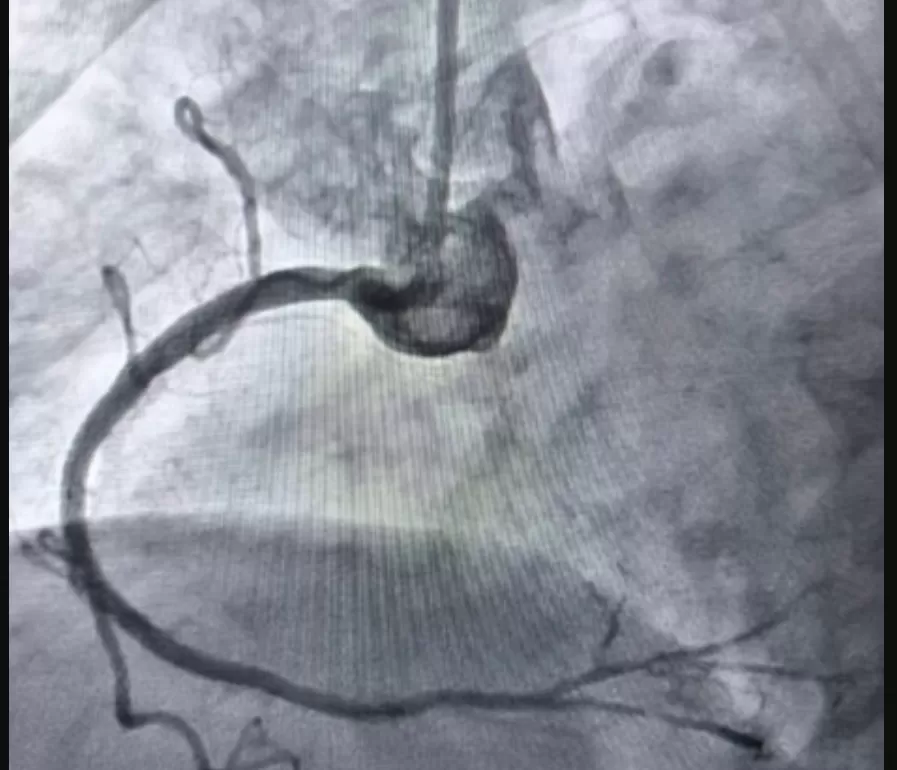

Як розповів завідувач відділення інтервенційної радіології, кардіології та реперфузійної терапії Богдан Маслій, у пацієнтки виявили значне звуження правої коронарної артерії. Розширити її традиційним балоном не вдалося, навіть при тиску до 25 атмосфер — це у десятки разів більше, ніж тиск у колесі автомобіля.

Тому лікарі застосували ротаблятор — спеціальний пристрій із діамантовим напиленням, який «шліфує» кальциновані бляшки та відкриває шлях для подальшого стентування. Саме цей метод дозволив усунути перешкоду в артерії та успішно встановити стенти.